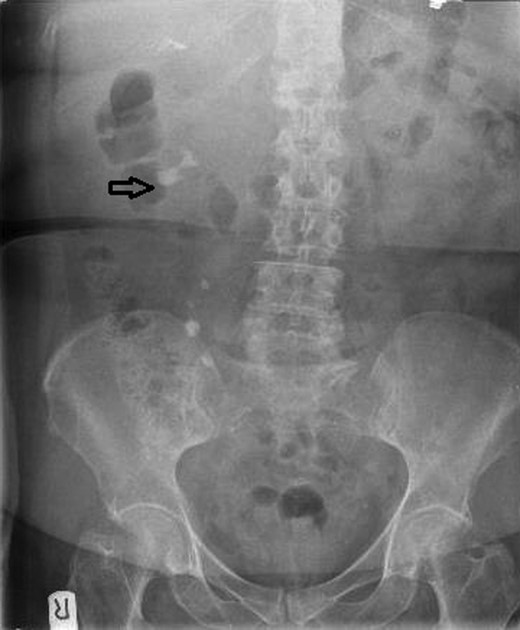

Urinalysis on admission was positive for blood and leukocytes, but subsequent urine culture failed to demonstrate any specific bacterial growth, possibly due to the fact that she had recently been on antibiotics. She had a raised white cell count (WCC) of 22.6 and C-reactive protein (CRP) of 158 on admission with normal renal function. An X-ray of her kidneys (XR-KUB) performed in the emergency department revealed a 2.7 cm partial staghorn stone in her right kidney likely occupying her lower pole calyx and possibly part of the renal pelvis (Fig. 1).